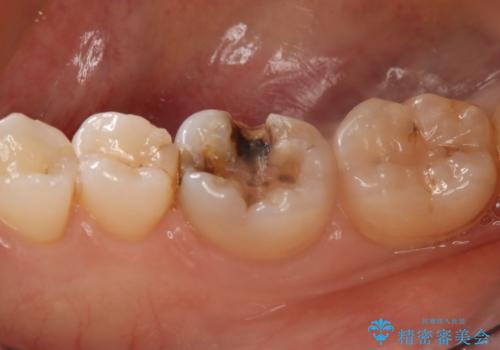

- 右下6番のメタルインレー脱離のため来院。

セラミックの治療を希望されたため切削量を考慮し、セラミックインレーでの治療を選択しました。

う蝕が深くまで進行していたので、CRで裏層した上で形成・印象をしています。